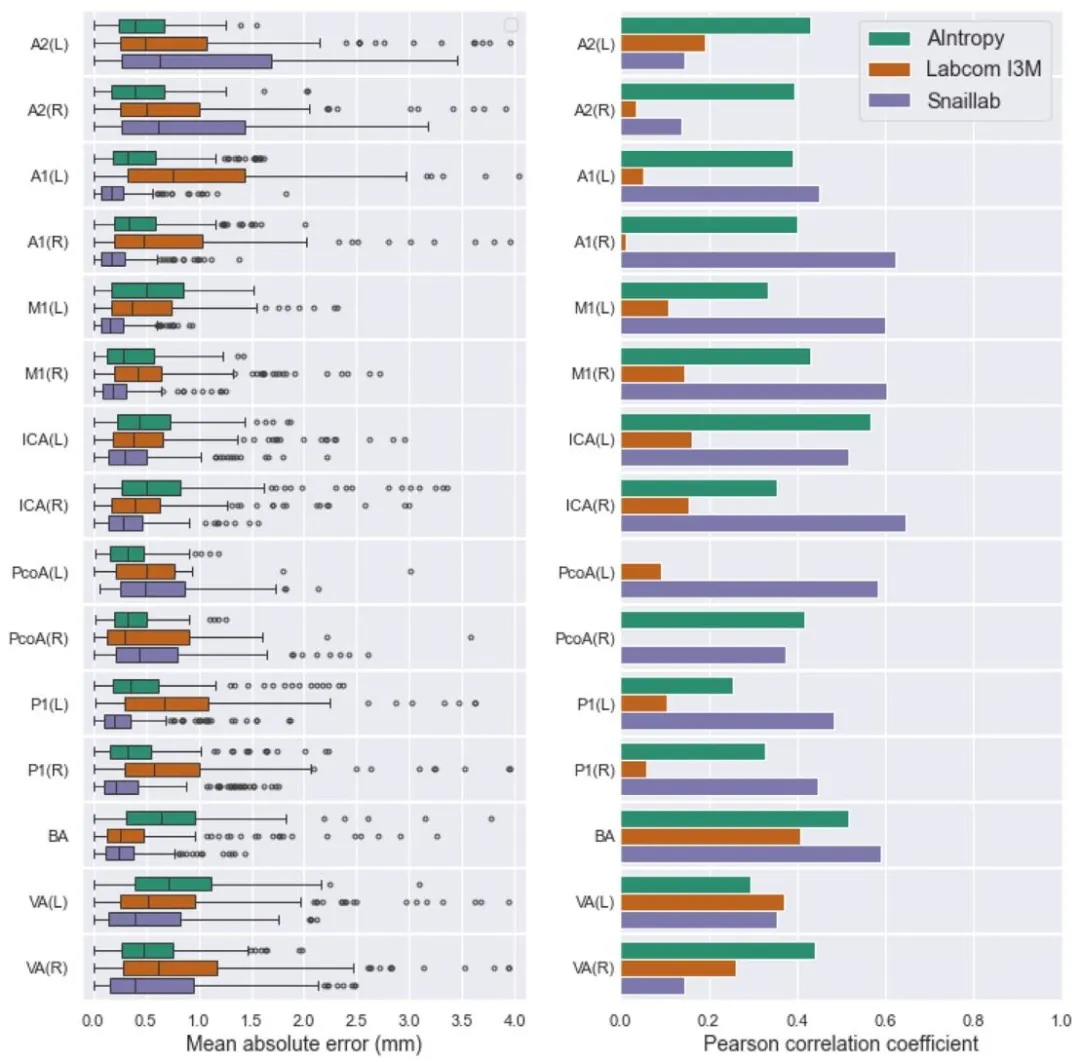

Fig. 6. Results of proposed solutions by each team for Task 2 (quantification of artery diameters and bifurcation angles) on the test set, shown per artery. Lower mean absoluteerror (MAE) and higher Pearson correlation coefficient are associated with better performance. The method of Labcom I3M yielded MAE scores exceeding 4.0 mm for all arteriesexcept the BA

图 6. 各团队针对任务 2(动脉直径和分叉角度量化)在测试集上按动脉分类的结果平均绝对误差(MAE)越低且皮尔逊相关系数越高,表明性能越好。Labcom I3M 团队的方法中,除基底动脉(BA)外,所有动脉的 MAE 得分均超过 4.0 毫米。